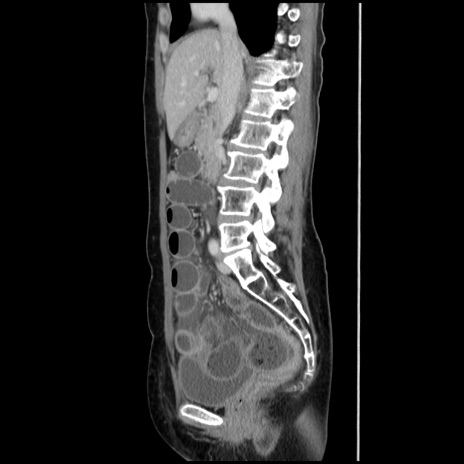

症例32(矢状断像)

横断像